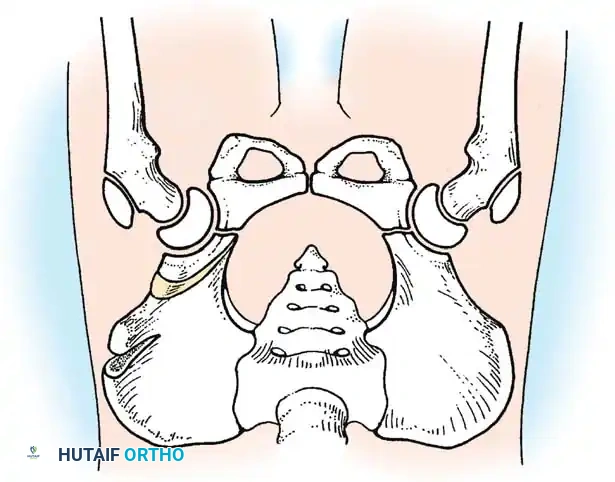

Fig 27-1: Ortolani maneuver for routine screening. The examiner stabilizes the pelvis, places the index and middle fingers over the greater trochanter, and gently abducts the hip.

Fig 27-2: Clinical signs of DDH in an older infant. Note the profound decrease in abduction (A) and the positive Galeazzi sign (B).

Radiographic evaluation: Normal hip anatomy (left) versus Dysplastic hip anatomy (right) demonstrating disruption of Shenton's line and an increased acetabular index.